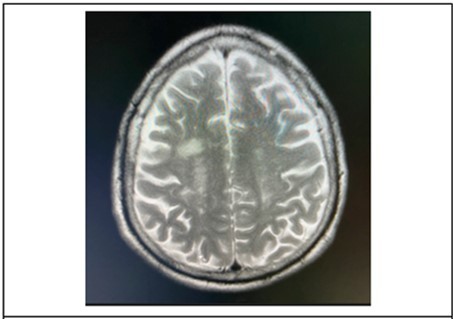

Cranial MRI plain and with contrast was requested by the ophthalmology service to further investigate on the brainstem. The subsequent study done 21 days after onset of symptoms, revealed patchy bright flair signals were noted in the subcortical white matter and periventricular area. (Figure 6) The orbits, midbrain, pons were regarded as unremarkable.

Figure 6.It showing T2 weighted, axial MRI scans at the level of the lateral ventricles, revealed patchy bright flair signals were noted in the subcortical white matter and periventricular area.

It showing T2 weighted, axial MRI scans at the level of the lateral ventricles, revealed patchy bright flair signals were noted in the subcortical white matter and periventricular area.